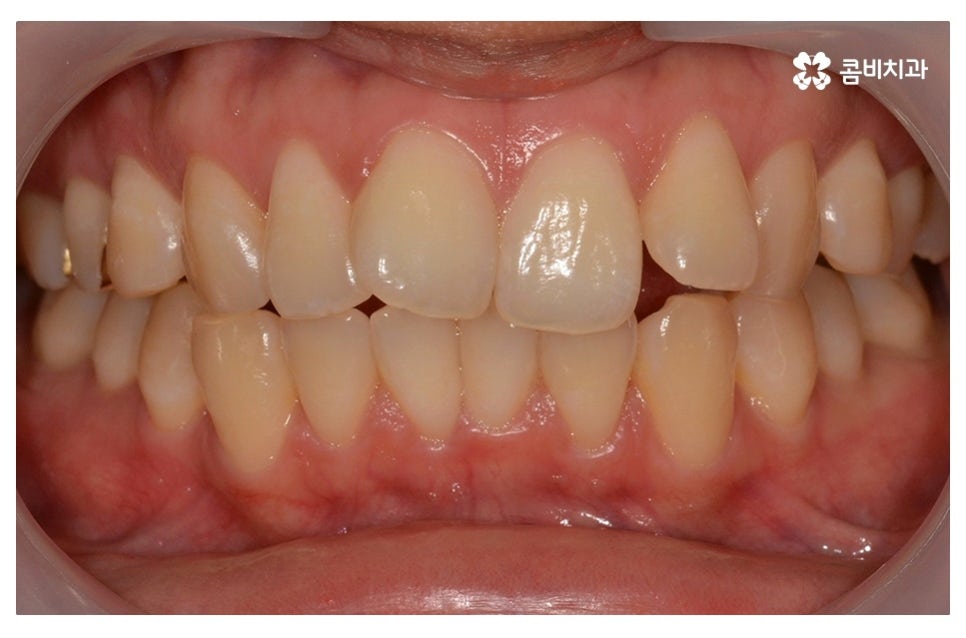

이번 포스팅에서 보인 덧니교정 사례의 경우 기능이 적은 작은 어금니를

발치하여 교정이 진행되었으며 발치를 진행하는 경우

작은 어금니를 발치하는데 충치 등으로 인해 손상이 큰 치아를

발치하는 경우가 일반적이라고 할 수 있어요.

물론 구강 내 치아의 이동 공간이 충분한 경우에는 비발치로도

덧니교정이 진행되는 경우도 있으며 덧니가 심하지 않은 경우에는

부분교정으로 치료가 진행되는 사례도 있어요.

위 환자분의 경우 덧니교정에 걸린 치료 기간은 약 24개월 정도이며

성인 이후에 치료를 진행한 사례라고 볼 수 있어요.